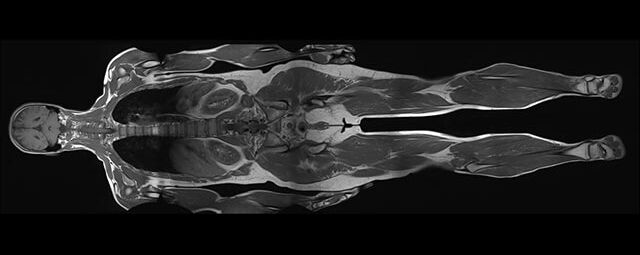

Magnet­resonanz­tomographie (MRT)

Die Magnetresonanztomographie (MRT) wurde als bildgebendes Verfahren ab 1973 vor allem von Paul C. Lauterbur und Sir Peter Mansfield entwickelt.

In den letzten Jahren hat sich die Methode stark weiterentwickelt und in der medizinischen Diagnostik etabliert.

Im Magnetresonanztomographen liegt die zu untersuchende Person in einem starken, homogenen Magnetfeld. Dieses Magnetfeld bewirkt eine gemeinsame Ausrichtung der Wasserstoffprotonen im Körper entlang der Längsachse des Magnetfeldes. Wird nun diesen Teilchen Energie in Form von Radiowellen in einer genau abgegrenzten Frequenz zugeführt, so werden sie aus ihrer ursprünglichen Orientierung abgelenkt.

Die zugeführte Energie wird in gewebespezifischer Weise wieder abgegeben. Ein hochempfindliches Computersystem misst die unterschiedliche Energieabgabe und setzt sie in Bildinformationen um. Jede Körperregion kann somit durch Schnittbilder in allen Raumebenen oder durch dreidimensionale Rekonstruktionen mit einem exzellenten Weichteilkontrast dargestellt werden. Es besteht keine Belastung durch Röntgenstrahlen.